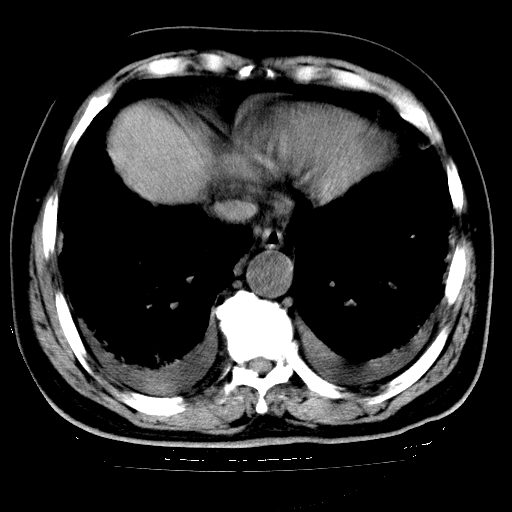

男,68岁,咳嗽、胸闷、发烧三天,查体:双肺散在湿罗音。

首先考虑特发型肺间质纤维化;两侧少量胸腔积液。

依据:1、两肺广泛条索状、网格状、蜂窝状改变。

5.双侧胸腔少量积液;双侧胸膜增厚。

双肺多发条索状、网格状及小灶状密度增高影。考虑慢支合并感染.间质纤维化,双侧少量胸腔积液

两肺广泛条索状、网格状、蜂窝状改变。肺间质纤维化,肺心病,双侧胸腔积液